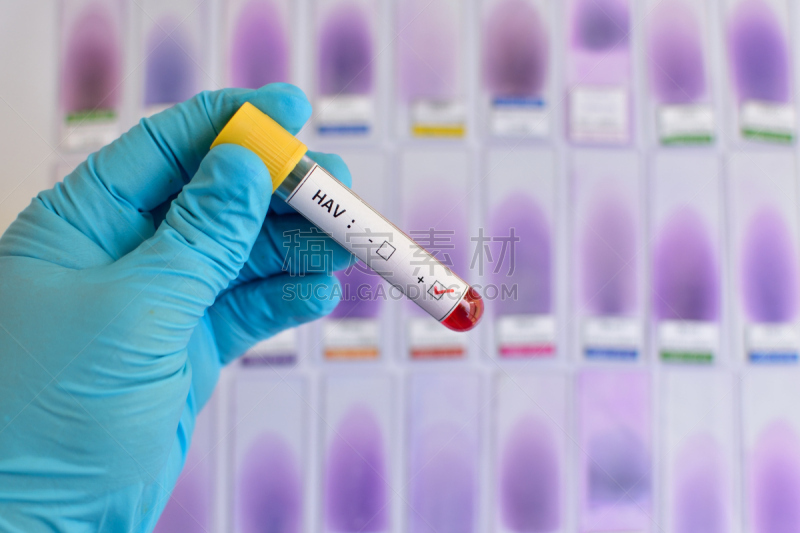

预防肝炎详情

肝炎详情